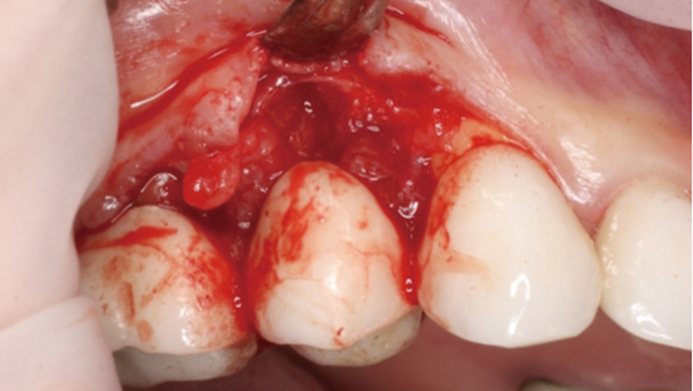

Clinical case: Extraction, immediate implant placement, & provisionalization

- Courtesy of Dr. Iulian Filipov, Romania -

Keywords

AnyRidge, R2GATE, guided surgery, immediate placement, immediate provisionalization, initial stability, Dr. Iulian Filipov, #25, maxillary posterior, immediate loading, Mega ISQ

Products:

AnyRidge implant system, R2GATE, MEGA ISQ, Digital prosthesis